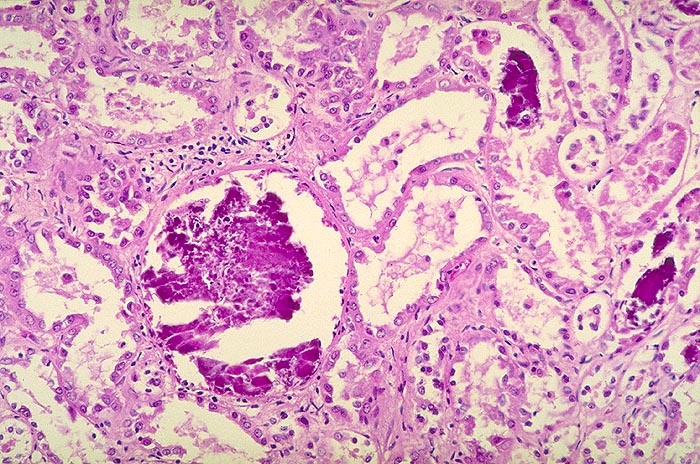

AP/ Nephrokalzinose

Nephrokalzinose

Niere

Pathologischer Befund